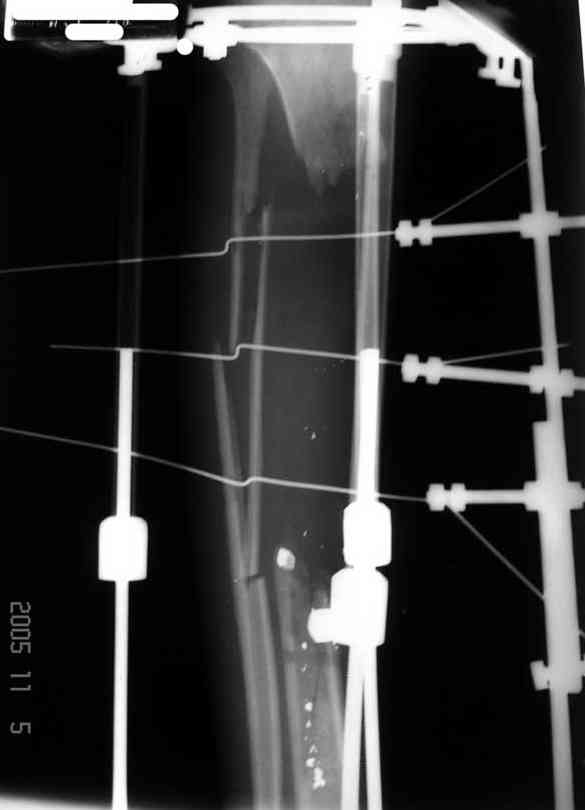

Илизарова (как придется), хирургически обработали и героически заживляли мягкие ткани с многочисленными кожными пластиками. В итоге через полгода я принял его вот таким:

Реализовал описанную выше методику, и в итоге вот что получилось. Высылаю лишь прямые проекции,

Рентген в процессе перемещения - внизу карбоновые кольца, тракция фрагмента спицами с упором.